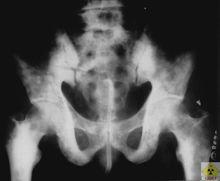

3.X線檢查應注意骨破壞範圍、程度及界限,有無骨膜反應,有無瘤骨形成及有無軟組織陰影。必要時應行CT、MRI檢查及血管造影。